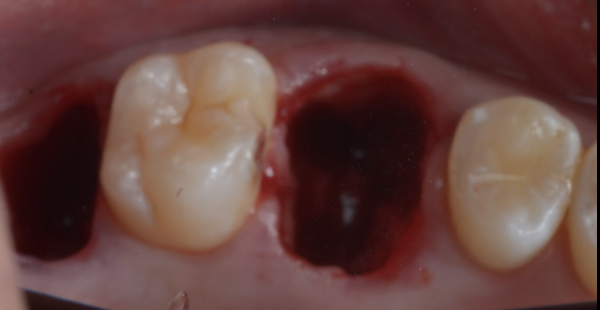

4)移植床形成 → ドナー歯抜歯 → 移植

口腔外時間や試適回数を最小化し、歯根膜ダメージを抑えることを最優先に進めます。